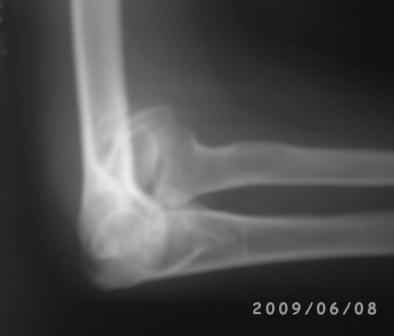

Уважаемые коллеги! Обратился больной 17 лет с жалобами на деформацию пр. локтевого сустава.

Травму получил 7 лет назад. Локально: вальгусная деформация л/с под углом 45гр., сгибание -30, разгибание-170гр., наружный мышелок плеча под пальцами подвижен, что интересно- мышелок плеча при пронации и супинации п/плечья вместе с головкой луча поднимается и опускается( см снимки).

Для интереса представляю снимки.

Уважаемый Андрей Волна, я очень рад Вас услышать.

Вы очень конкретно и правильно поставили вопросы и очень аргументированно анализировали, смысл мне понравился, дело в том что у меня был случай 4-года назад. Б-ная 18 лет, травму получила в детстве, клиника точно такая, только движения в плече-лучевом суставе была сохранена, произведена клиновидная надмышелковая остеотомия, фиксация спицами и тогда была наложена гипсовая повязка на 1,5месяца, разработка движений начался очень хорошо, и она уехала в другой город, где оказывается удалили спицы и она доволно результатом.( ложный сустав латераль. мышелка так и осталось и ей не мешает!)

Кликните для загрузки файла 1 (1).jpg

50KB (51630 bytes)